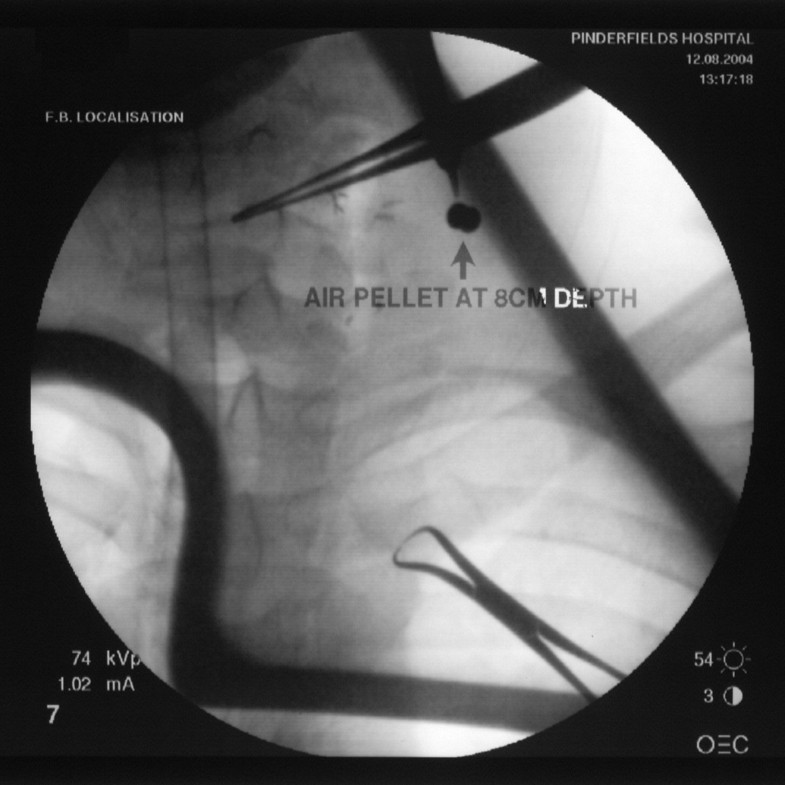

Air Gun Pellets Wound . A plain chest radiograph demonstrated the pellet. the management of thoracic/cardiac pellet gun injuries should be based on the presentation and stability of the patient. The airgun pellet caused a defect in the. we present a case of a potentially fatal airgun injury to the neck. traumatic embolization of pellets into the cerebral circulation is a rare complication following gunshot wounds to. physical examination revealed a small entry wound in the right axilla. 1 most modern air weapons exceed this velocity and many air rifles can deliver a projectile with similar muzzle velocity to a conventional hand gun. we describe a 21 year old man who sustained a penetrating cardiac.